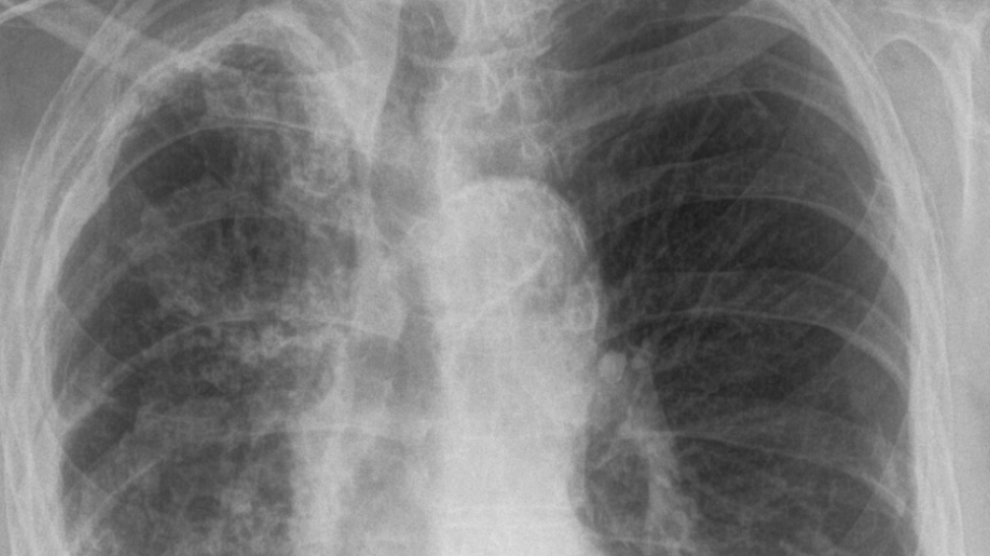

Tuberkuloza je bolest koja se danas dosta lako dijagnosticira. Važno je uzeti dobru anamnezu i obaviti pregled pacijenta, načiniti laboratorijske nalaze i RTG snimak pluća. Analiza biološkog materijala na tuberkuloznu klicu i dalje ostaje prva metoda za postavljanje dijagnoze –...